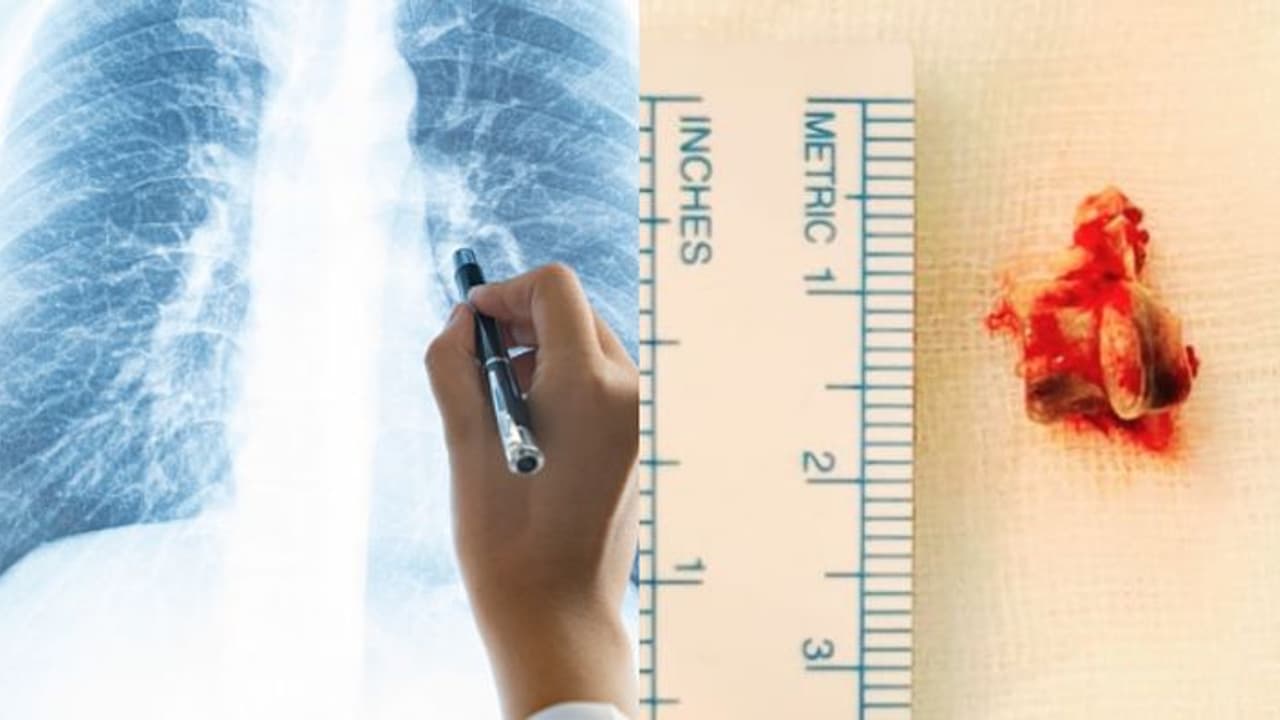

കൊച്ചി: ശ്വാസകോശത്തിൽ നിന്ന് കണ്ടെത്തിയത് കോഴിക്കറിയിലെ എല്ല്. മൂന്ന് വർഷമായി ശ്വാസകോശ സംബന്ധിയായ ബുദ്ധിമുട്ടുകൾ കൊണ്ട് വലഞ്ഞ പെരുമ്പാവൂർ സ്വദേശിയായ 62കാരന്റെ ശ്വാസകോശത്തിൽ നിന്നാണ് കറിയിൽ നിന്നുള്ള എല്ല് നീക്കം ചെയ്തത്. വളരെ നീണ്ട് നിൽക്കുന്ന ചുമയും ശ്വാസതടസവും ഇടവിട്ടെത്തുന്ന പനിയുമായിരുന്നു 62കാരനെ വലച്ചിരുന്നത്. രണ്ട് ആഴ്ച മുൻപാണ് 62കാരൻ വിദഗ്ധ ചികിത്സ തേടി അമൃത ആശുപത്രിയിൽ എത്തിയത്. എക്സ് റേ പരിശോധനയിലും സി ടി സ്കാനിലും ശ്വാസകോശത്തിൽ അന്യവസ്തുവുള്ളതായി കണ്ടെത്തുകയായിരുന്നു. ശ്വാസകോശത്തിന്റെ വലത്തേ നാളിയുടെ താഴ്ഭാഗത്താണ് എല്ല് കുടുങ്ങിയത്.

അന്യവസ്തുവിന് പുറമേയ്ക്ക് ദശ വന്ന നിലയിലായിരുന്നു എല്ലിന്റെ ഭാഗമുണ്ടായിരുന്നത്. ഫ്ലെക്സിബിൾ ബ്രോങ്കോസ്പി എന്ന രീതിയിലൂടെയാണ് എല്ലിൻ കഷ്ണം കണ്ടെത്തിയത്. ദ്രവിച്ച് രണ്ട് ഭാഗങ്ങളായി മുറിഞ്ഞ അവസ്ഥയിലാണ് എല്ല് പുറത്തെടുത്തത്. രണ്ട് സെന്റിമീറ്ററോളം നീളമുള്ള എല്ലിൻ കഷ്ണമാണ് പുറത്തെടുത്തത്. എക്സ് റേ പരിശോധനയിൽ ശ്വാസകോശത്തിൽ അന്യ വസ്തു കണ്ടെത്തിയതിന് പിന്നാലെയാണ് ഇയാൾ വിദഗ്ധ ചികിത്സ തേടി കൊച്ചിയിലെത്തിയത്.